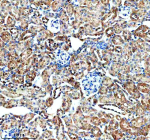

IHC analysis of GHRHR using anti-GHRHR antibody. GHRHR was detected in a paraffin-embedded section of human ovarian cancer tissue. Heat mediated antigen retrieval was performed in EDTA buffer (pH 8.0, epitope retrieval solution). The tissue section was blocked with 10% goat serum. The tissue section was then incubated with 2 ug/ml rabbit anti-GHRHR antibody overnight at 4oC. Peroxidase Conjugated Goat Anti-rabbit IgG was used as secondary antibody and incubated for 30 minutes at 37oC. The tissue section was developed using an HRP secondary and DAB substrate.